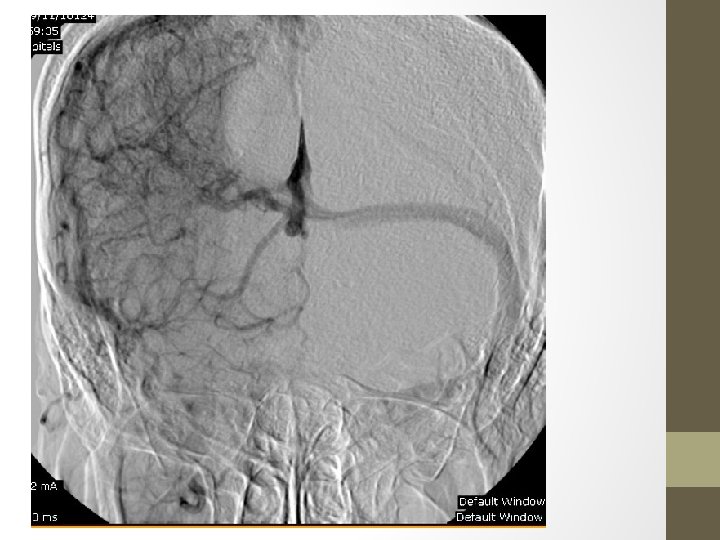

Cerebral Venous Angioma(DVA) • A congenital malformation of veins which drain normal brain • Most common cerebral vascular malformation • Characterised by the caput medusae sign(collection of dilated medullary veins converge in an enlarged transcortical or subependymal collector vein) in angiography. The appearance has also been likened to a palm tree • Usually incidental findings but patients can present with intracranial haemorrhage(1 -5%) and also with ischaemic stroke and epilepsy. • Most common location: frontoparietal region (36 -64%) • %75 solitory lesions but %20 of cases are associated with cavernous malformations and are referred to as mixed vascular malformations (MVM)